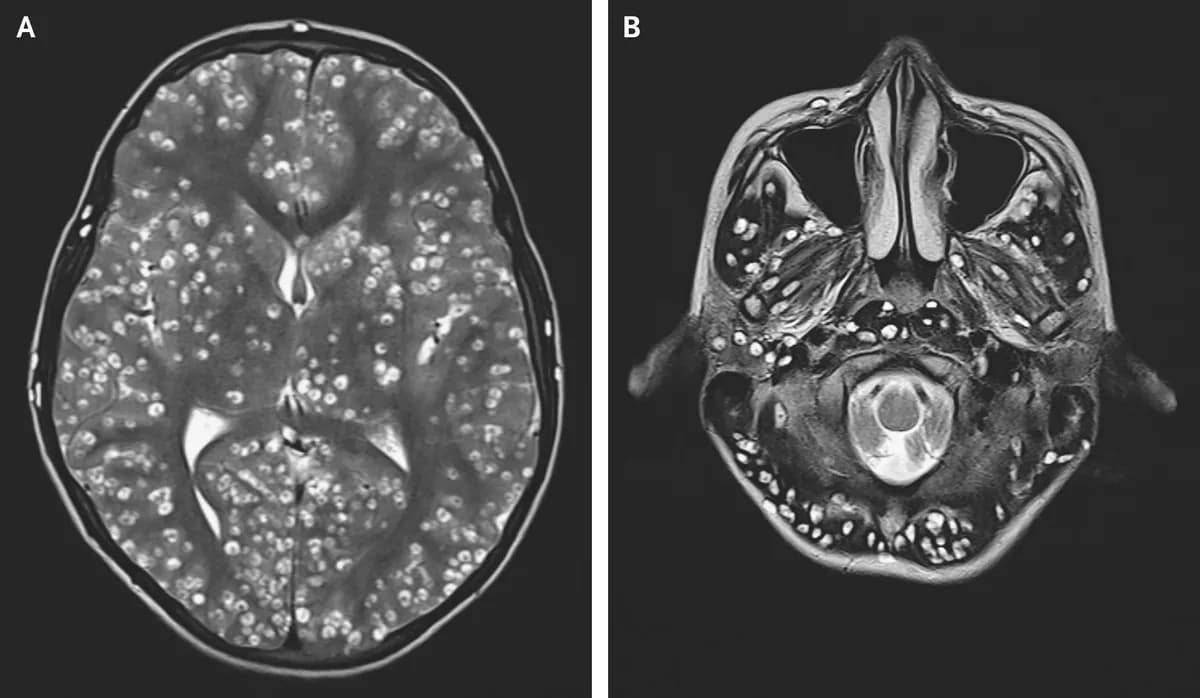

O que é Neurocisticercose cerebral? Descubra como essa condição pode afetar o cérebro humano